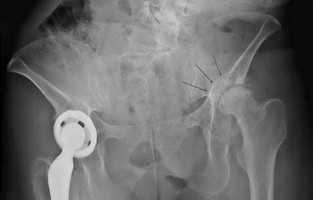

A 72-year-old female undergoes a primary total hip arthroplasty via a posterior approach. Postoperatively, she experiences recurrent posterior dislocations. Radiographic evaluation demonstrates an anteverted cup at 15 degrees and an abduction angle of 40 degrees, with the femoral stem in 5 degrees of retroversion. What is the most likely cause of her instability?

Correct Answer: Femoral component retroversion

Explanation:

Stability in total hip arthroplasty is largely dependent on the combined anteversion of the acetabular and femoral components, which should optimally be between 25 and 35 degrees (Widmer's criteria). In this case, the acetabular cup is anteverted 15 degrees, but the femoral stem is retroverted 5 degrees, resulting in a combined anteversion of only 10 degrees. This relative retroversion significantly increases the risk of posterior dislocation.